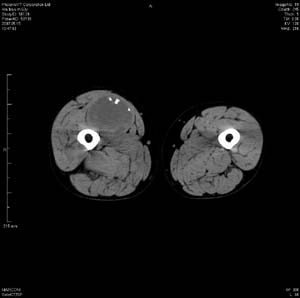

男 63岁 右大腿无痛性肿块11年,x片右大腿软组织肿块影,余无明显异常.ct值-13__239hu

右大腿股内侧股与收肌间隙间多发囊实性占位,界清.内示斑点状钙化.局部骨质无异常.肌肉推压移位表现.

考虑肌间隙病变.可有1,神经来源肿瘤.2,血管来源病变.3,淋巴来源肿瘤.4,脂肪来源肿瘤.5,滑膜来源肿瘤.结合病史只能考虑良性占位.建议增强或mri进一步分析.

同意,病史较长,病变周围分界清晰,考虑良性病变。病灶内有多发斑点状钙化,沿肌间隙生长,血管瘤或淋巴管瘤首先考虑。